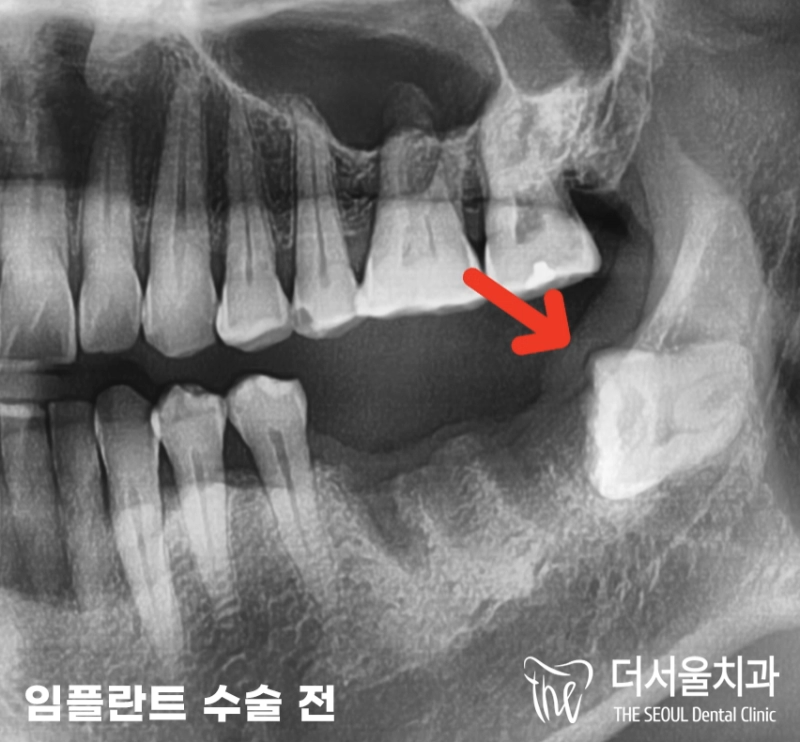

반갑습니다. 판교역 더서울 치과 쌍둥이 박현성 원장입니다. 오늘 보여드릴 임플란트 케이스는 조금 특이했다고 말씀드릴 수 있는데요. 환자분께서는 초등학교를